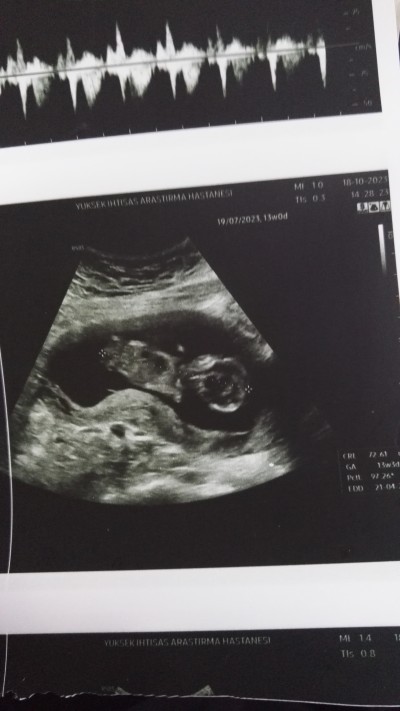

13+1 haftalık

image